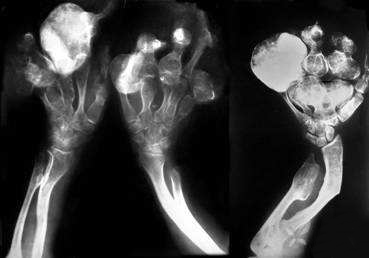

病变为多发,难以治疗每个内生软骨瘤,对无症状者可不治疗,仅随诊观察。对有症状的具体部位,可刮除病灶并植骨,有明显的肢体畸形者可做截骨纠正。也有一些病例,特别是手指,会继续发展,成为奇形怪状的异常形态。若这些畸形手指有功能障碍,可切除最严重的病变的手指,但切除拇指,要非常慎重。

多发内生软骨瘤病人随着生长,病变可缩小甚至完全消失,被正常组织代替。另一方面,这种病变潜伏着恶性改变的可能性,可变为软骨肉瘤或骨肉瘤,恶变一旦发生,或己形成明显的软骨肉瘤,应采取较彻底的手术方法予以切除,甚至截肢。多发内生软骨瘤病具有潜在恶性变的可能,恶变为软骨肉瘤或骨肉瘤,应引起注意。